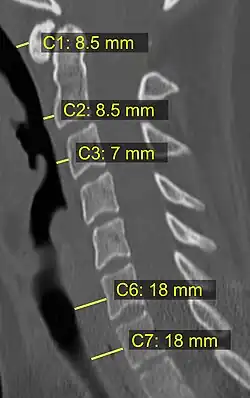

Na tomografia computadorizada ou radiografia, uma fratura cervical pode ser visualizada diretamente. Além disso, sinais indiretos de lesão pela coluna vertebral são incongruências das linhas vertebrais,[6] e/ou aumento da espessura do espaço pré-vertebral:[7]